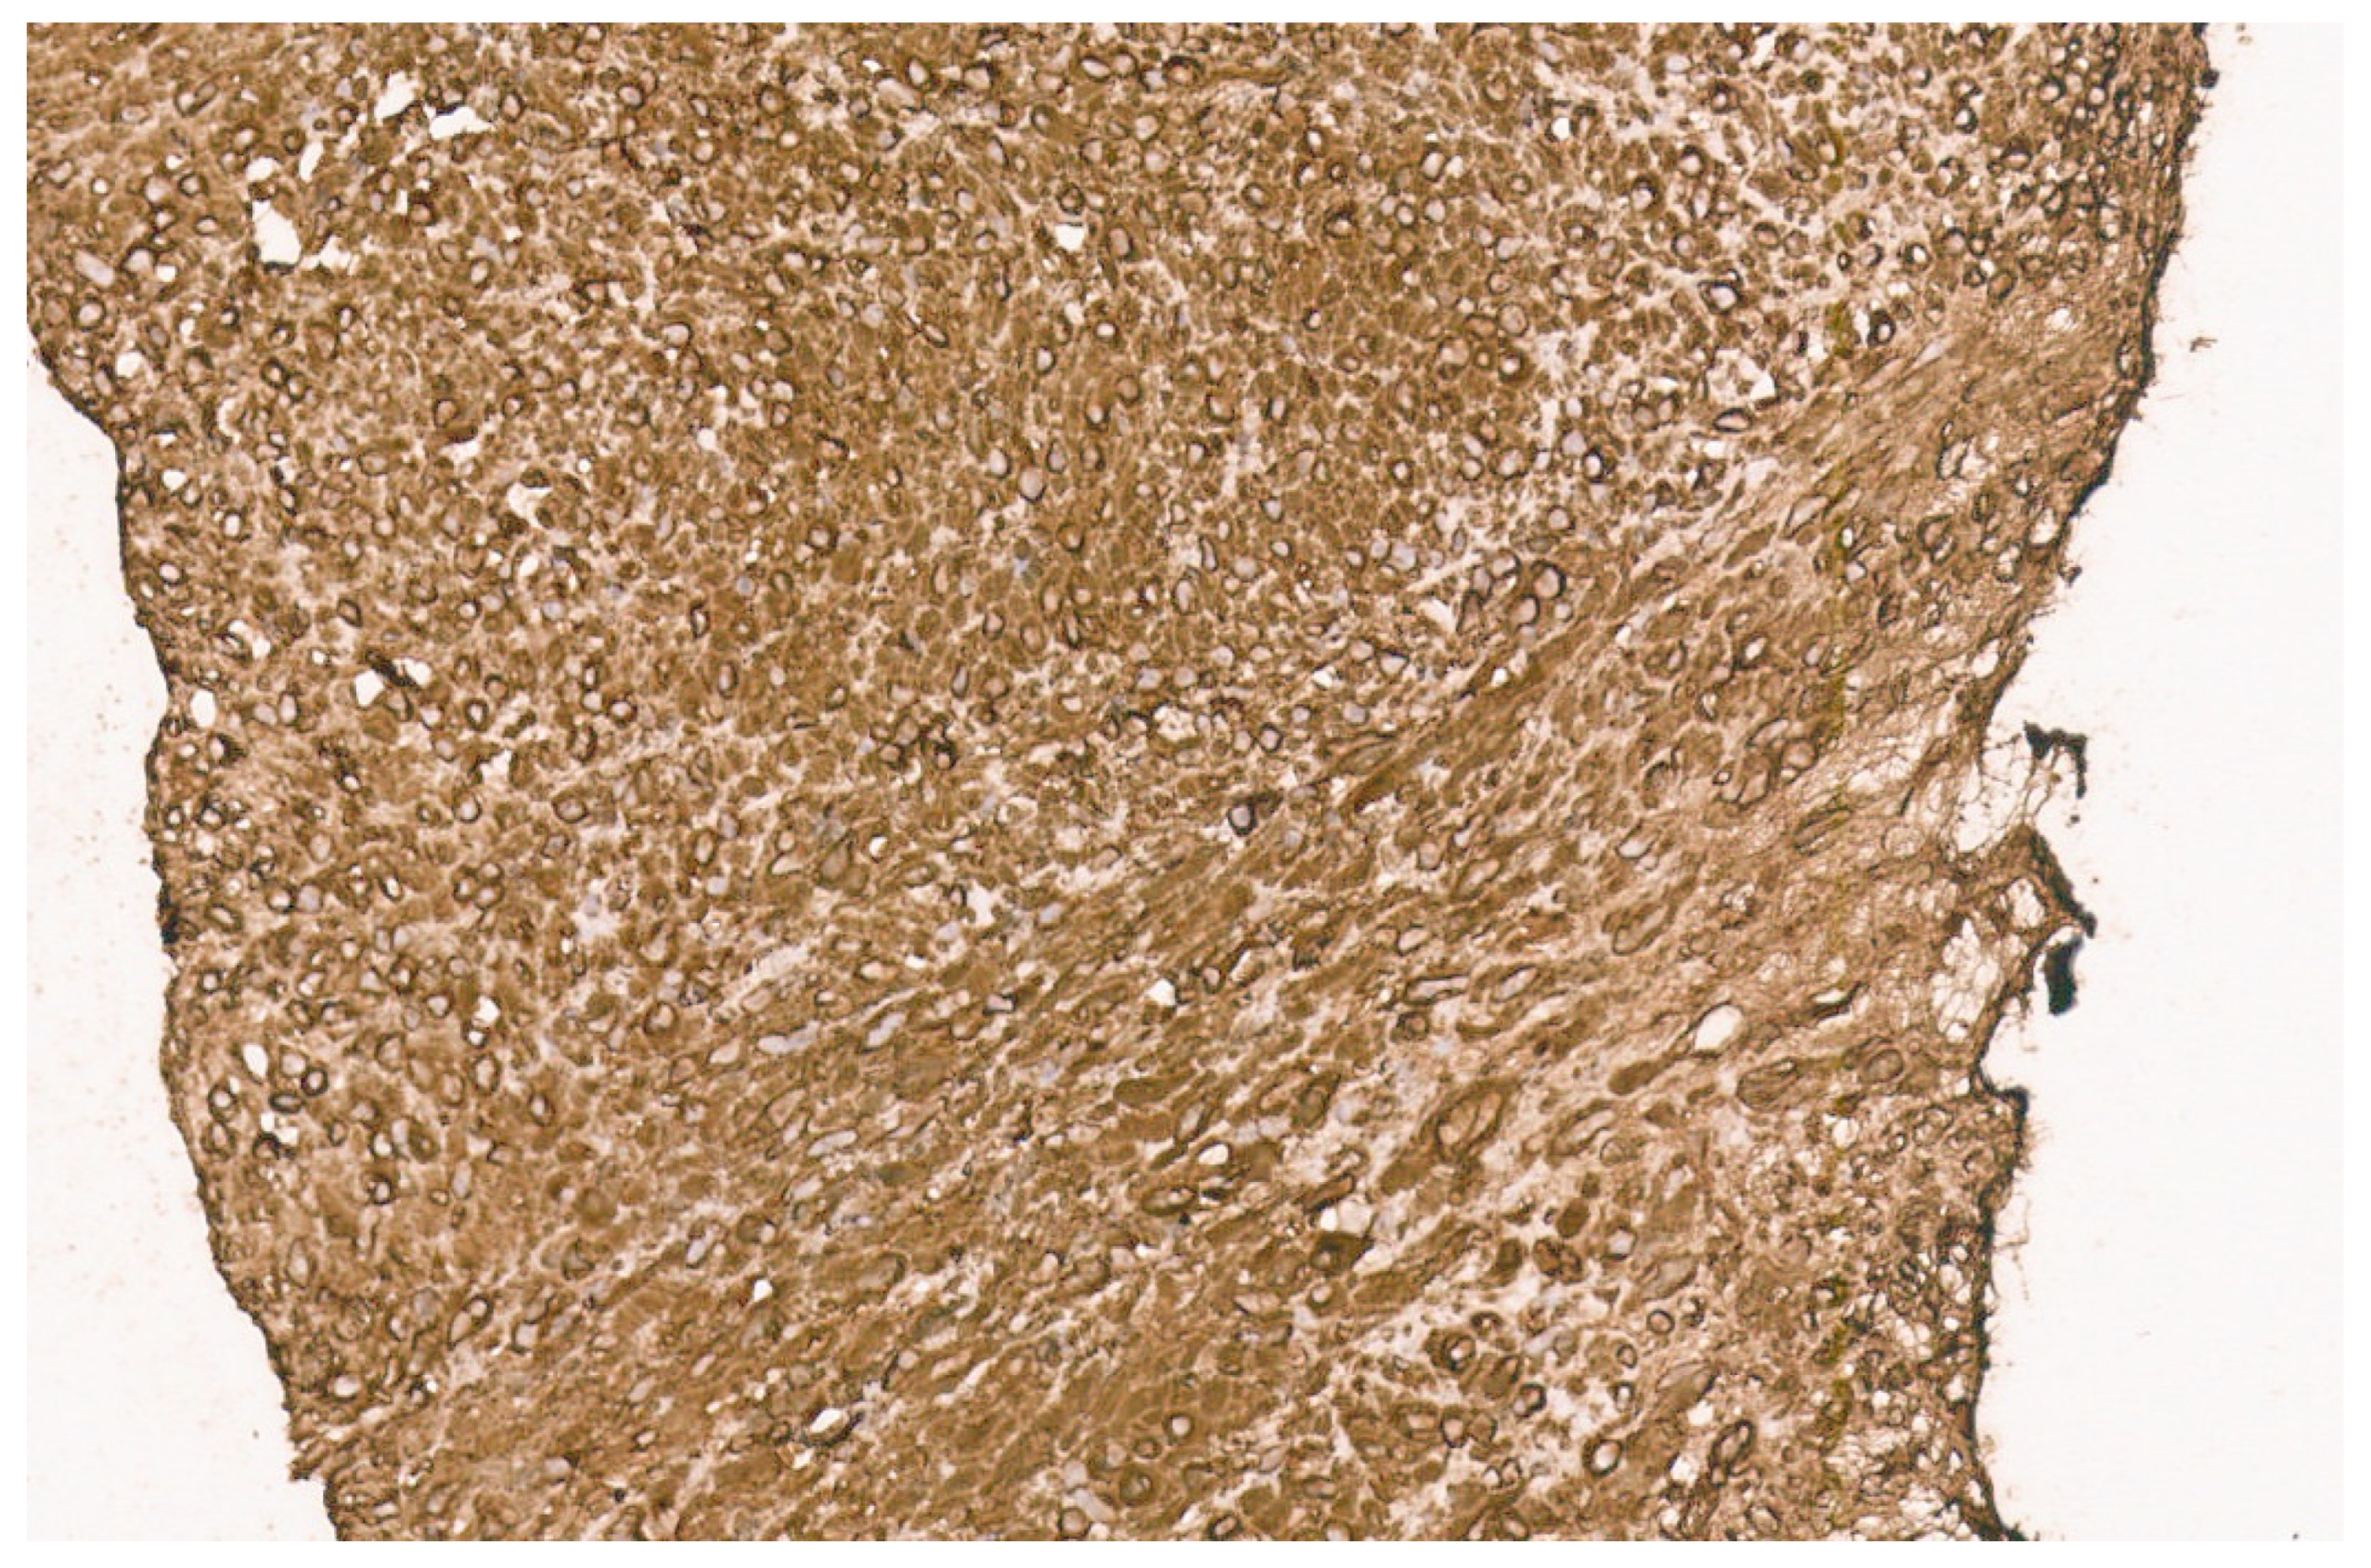

12.3. Pathology